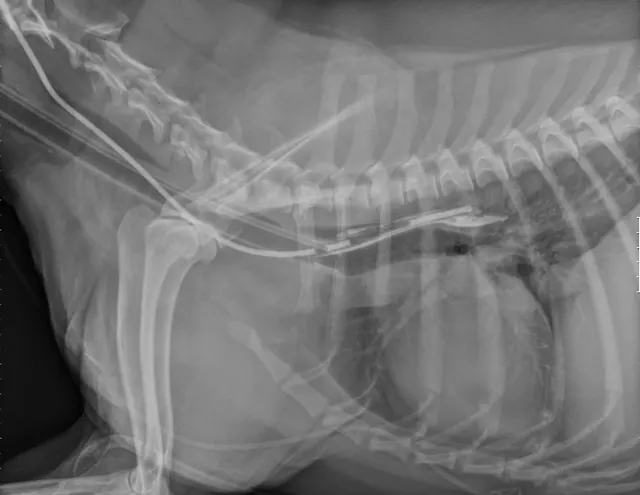

If the tube is in the trachea, the portion running in the proximal cervical region will be visibly ventral to the esophagus on radiography (C).